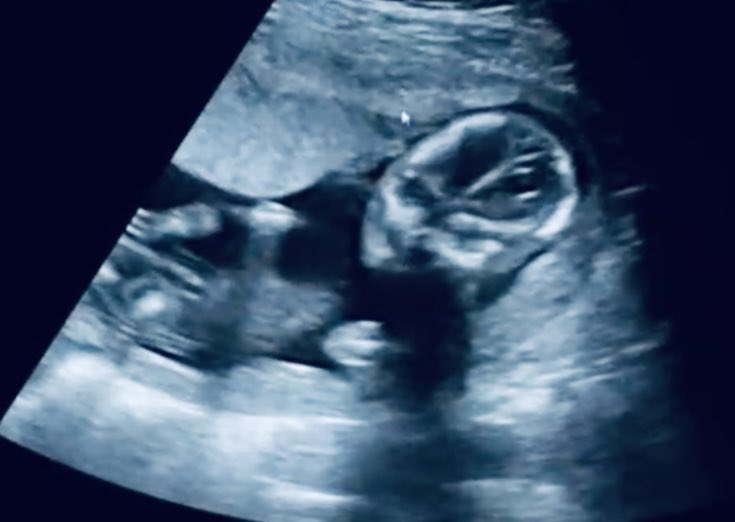

妊娠5ヶ月(17週)の体調とお腹の写真妊娠中期 妊婦健診4回目のエコー写真では手の動きをよくみることができました! そして逆子が判明! この時期はお腹の中でよくクルクル回るそうなので、そこまで気にしなくても良いと言われました。 週目 妊娠4ヶ月目(12~15週) 胎盤がほぼ完成し、へその緒を通して母体から酸素や栄養をもらうようになります。 骨や筋肉が急速に発達し、エコーでもしっかりした背骨が確認できます。 眉毛やまつ毛などの体毛が生え始めるほか、生殖器が作られる時期で妊娠15週1日(15w1d)の超音波(エコー)写真 大きさ順調と言われました!つわりもおさまって楽しく正月が迎えられそう(*^^*) 先生に性別聞いたら、まだ小さいからハッキリとはわからないけど股の間に何かあるかんじではあるね♪と一言。

妊娠15週は妊娠4ヶ月の4週目。「妊娠初期」と呼ばれる時期の最後の1週間です。お腹の 赤ちゃんもすくすく育ち、体重約100gの大きさに。 ママの つわり症状はおさまり、胎盤が完成し、安定期はもう目前です。 妊娠中期を迎えるにあたっての注意点も含めながら、妊娠15週の赤ちゃんとママの体妊娠14週のお腹の赤ちゃんの大きさ 妊娠14週ごろのお腹の赤ちゃんの大きさは、 身長は10~12cm ほど。 体重は約60g でまだまだ小さいですが、ママの子宮の中で日々発育しています。 ※9週0日まではcrl(頭殿長)、10週0日以降はbpd(児頭大横径)の値になります。 ※CRLは50 パーセンタイル の値です。 ※BPDは標準偏差(SD)が標準(±0)の値です。